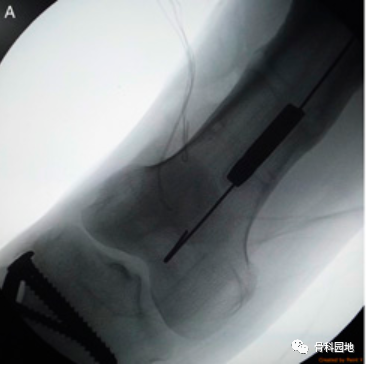

从长骨干取除断裂的髓内钉仍然是一个棘手的问题。本文介绍一种方法,该方法在技术上比文献中描述的其他方法要求低。此方法类似于钓鱼,这是一种通过鱼钩钓鱼的方法。在这种方法中,断裂的钉子在透视引导下钩住,并通过由不锈钢丝制成的钉钩以逆行方式取回。它无创地去除断裂的钉子,需要进一步暴露。1.首先钩子有一个宽阔的嘴,一个窄的弯曲(图A,B)。

2.逆行的方式钩住并取回钉子(图A,B)。

钓鱼技术用于取回髓内钉远端断裂部分。取了一根 20 号长的不锈钢线,其长度足以到达并取回断裂的钉子。如上所述,在其一端制作了一个钉钩。将去除的钉子近端部分用作模板,以按照所需的尺寸制作钩子。在透视引导下,钩子沿着髓管向下传递,然后穿过断裂的钉子,使得整个钩子位于钉子远端()。

然后将不锈钢丝拉近端以钩住断裂的钉子。然后通过轻轻地将不锈钢线拉出来取回钉子(图B)。